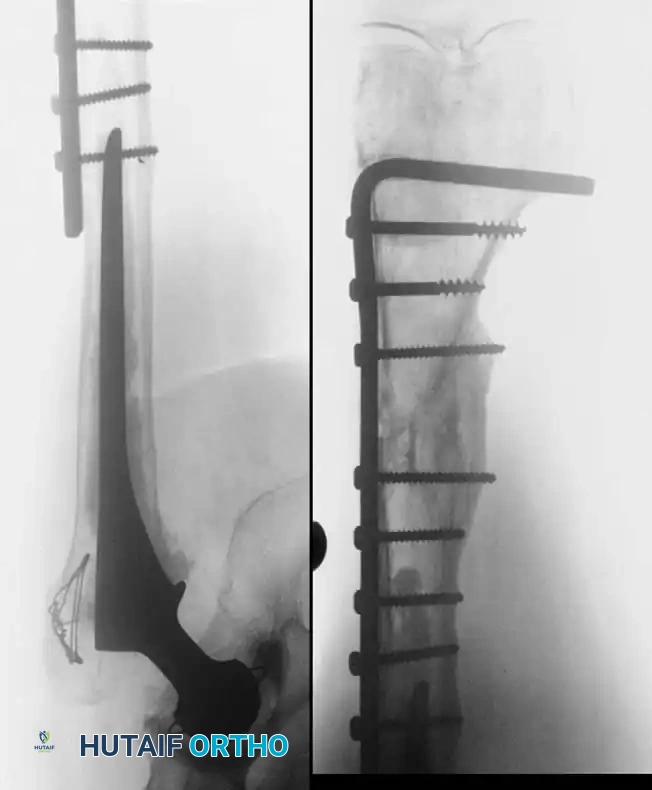

Associated Surgical & Radiographic Imaging